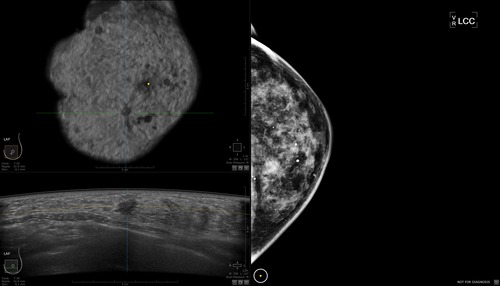

The automated breast ultrasound exam (ABUS), which was developed by GE Healthcare, takes about 15 minutes and remains the only technology for screening women with dense breasts approved by the FDA.

A comparison of a mammography image (right) and ABUS images (top and bottom on the left). Photo credit: GE Healthcare

Ultrasound, which uses sound waves to create images of the body, is valuable since it renders cancer black and eliminates the snowball effect. (Women with suspected cancer lesions may also undergo an MRI and biopsy.)